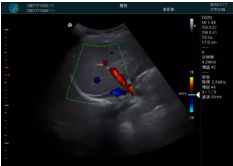

頸動脈血流充盈飽滿,無外溢

肝內(nèi)血管顯示清晰,血流敏感無外溢